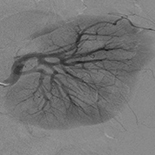

From 2007 to 2012, 20 patients were treated with superselective renal artery embolization for bleeding after percutaneous nephrolithotomy (PCNL), nephron-sparing surgery (NSS), including 1 patient with AVF after PCNL. During the procedure, embolization material was injected through a microcatheter to stop the bleeding. Embolization materials included a mixture of cyanoacrylate and lipiodol, embolization coils, and Spongostan. Clinical evaluation included remission of hematuria and normalization of blood morphotic elements.

The cause of bleeding into the urinary tract was damage to vessels (all cases): with coexisting false aneurism (8 cases); with coexisting arterio-venus fistula (1 case); and with coexisting intrarenal hematoma (3 cases). The bleeding occurred 2–5 days after PCNL and NSS, and 10 days after PCNL with AVF. The mean hematocrit level was 22%–24%. Technical success was achieved in 20 cases. Clinical success was achieved in 19 cases. One patient with hematuria after PCNL with AVF needed a second endovascular treatment to stop bleeding.